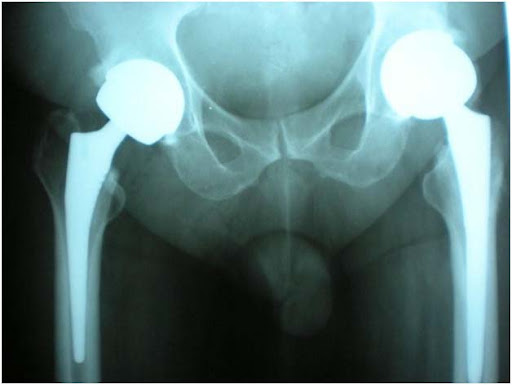

Birmingham Hip Resurfacing or Surface Replacement Arthroplasty is a bone-conserving alternative to conventional Total Hip Replacement (THR). Unlike Total Hip Replacement, Birmingham hip Resurfacing does not involve the removal of the femoral head and neck or removal of bone from the femur. Rather, the head, neck and femur bone is preserved in an effort to facilitate future surgery should it be necessary and to enable the patient to take advantage of newer technology or treatments in the future. The current generation of hip Resurfacing devices utilize a metal bearings have demonstrated a much higher level of wear resistance as well as reduced bone loss and inflammatory tissue reaction about the hip joint as compared to metal-polyethylene bearings.

Hip Resurfacing epitomizes medical achievements in arthroplasty. Hip Resurfacing is a new conservative surgical technique of arthroplasty of the hip. In this, only the diseased surface of the head of femur is replaced with a cobalt chromium cap , retaining all the bone in the hip joint. The lining of the socket (acetabulam) is also replaced with the cobachromium cup .This mimics the natural hip closely and has near normal bio-mechanics, load transfer and range of movement.

The BIRMINGHAM HIP Resurfacing (BHRT) device has two parts: a socket in the shape of a shallow cup (acetabular component), and a cap in the form of a ball head (femoral resurfacing component). The cup replaces the damaged surface of your hip socket (acetabulum). The cap covers the ball-shaped bone at the top of your thigh (femoral head), and the cap has a small stem that is inserted into the top of your thighbone. The cap moves within the cup. The surfaces that rub against each other (the bearing couple) are made from highly-polished metal. This type of bearing couple is called a metal-on-metal bearing couple.

The Birmingham Hip Resurfacing procedure is a bone-conserving technique that uses a two-part all-metal implant. Most importantly, the head of the femur and its’ neck are not removed as occurs in the traditional total hip replacement surgery. Instead, the Birmingham Hip Resurfacing surgery uses specialized tools to resurface the existing bone. The socket is shaped to accept a new cup, and an all-metal (not plastic) cup with a porous surface is inserted. The head of the femur is prepared to receive the new cup. The procedure involves shaving just a few millimeters of bone around the femoral head and a new metal cap is applied. The cap is made of cobalt chrome, a very durable material.